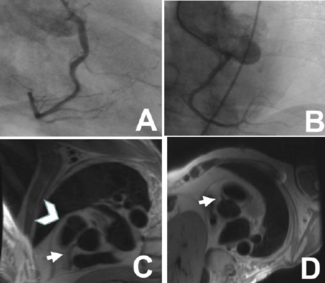

A. Shaheer Ahmed, MD, DM, DNB; Tushar Agarwal, MD

A 45-year-old man presented with complaints of chest pain for 6 hours.